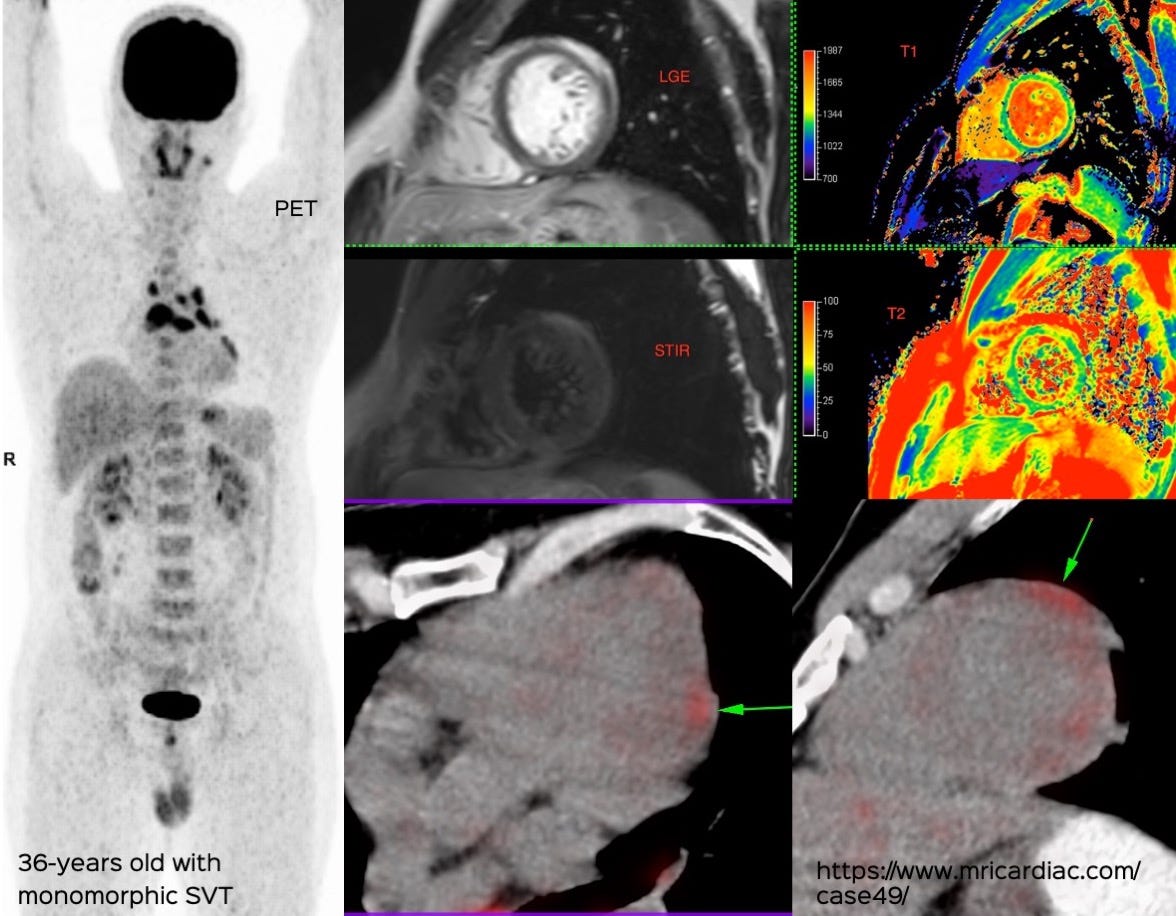

https://www.ctchestreview.com/case62/